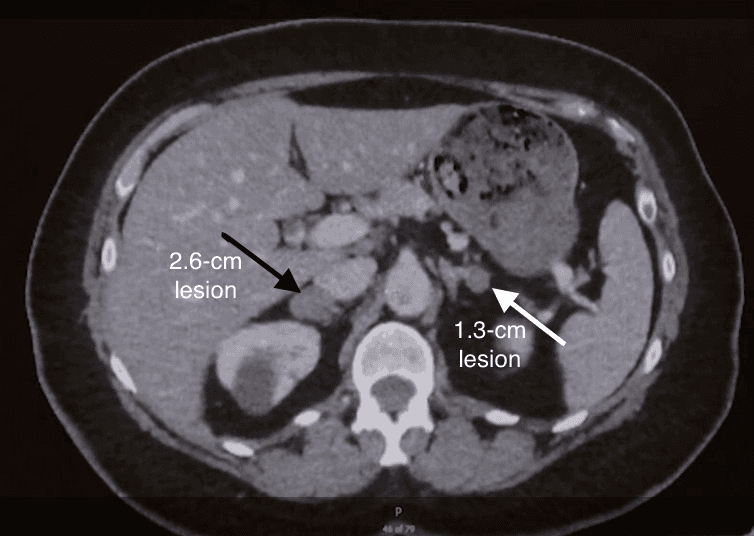

An abdominal CT revealed a 2.6-cm lesion in the right adrenal gland and a 1.3-cm lesion in the left adrenal gland (Figure 1).

Noncontrast abdominal CT revealing a 2.6-cm lesion consistent with a right adrenal mass (black arrow), and a 1.3-cm lesion consistent with a left adrenal mass (white arrow).